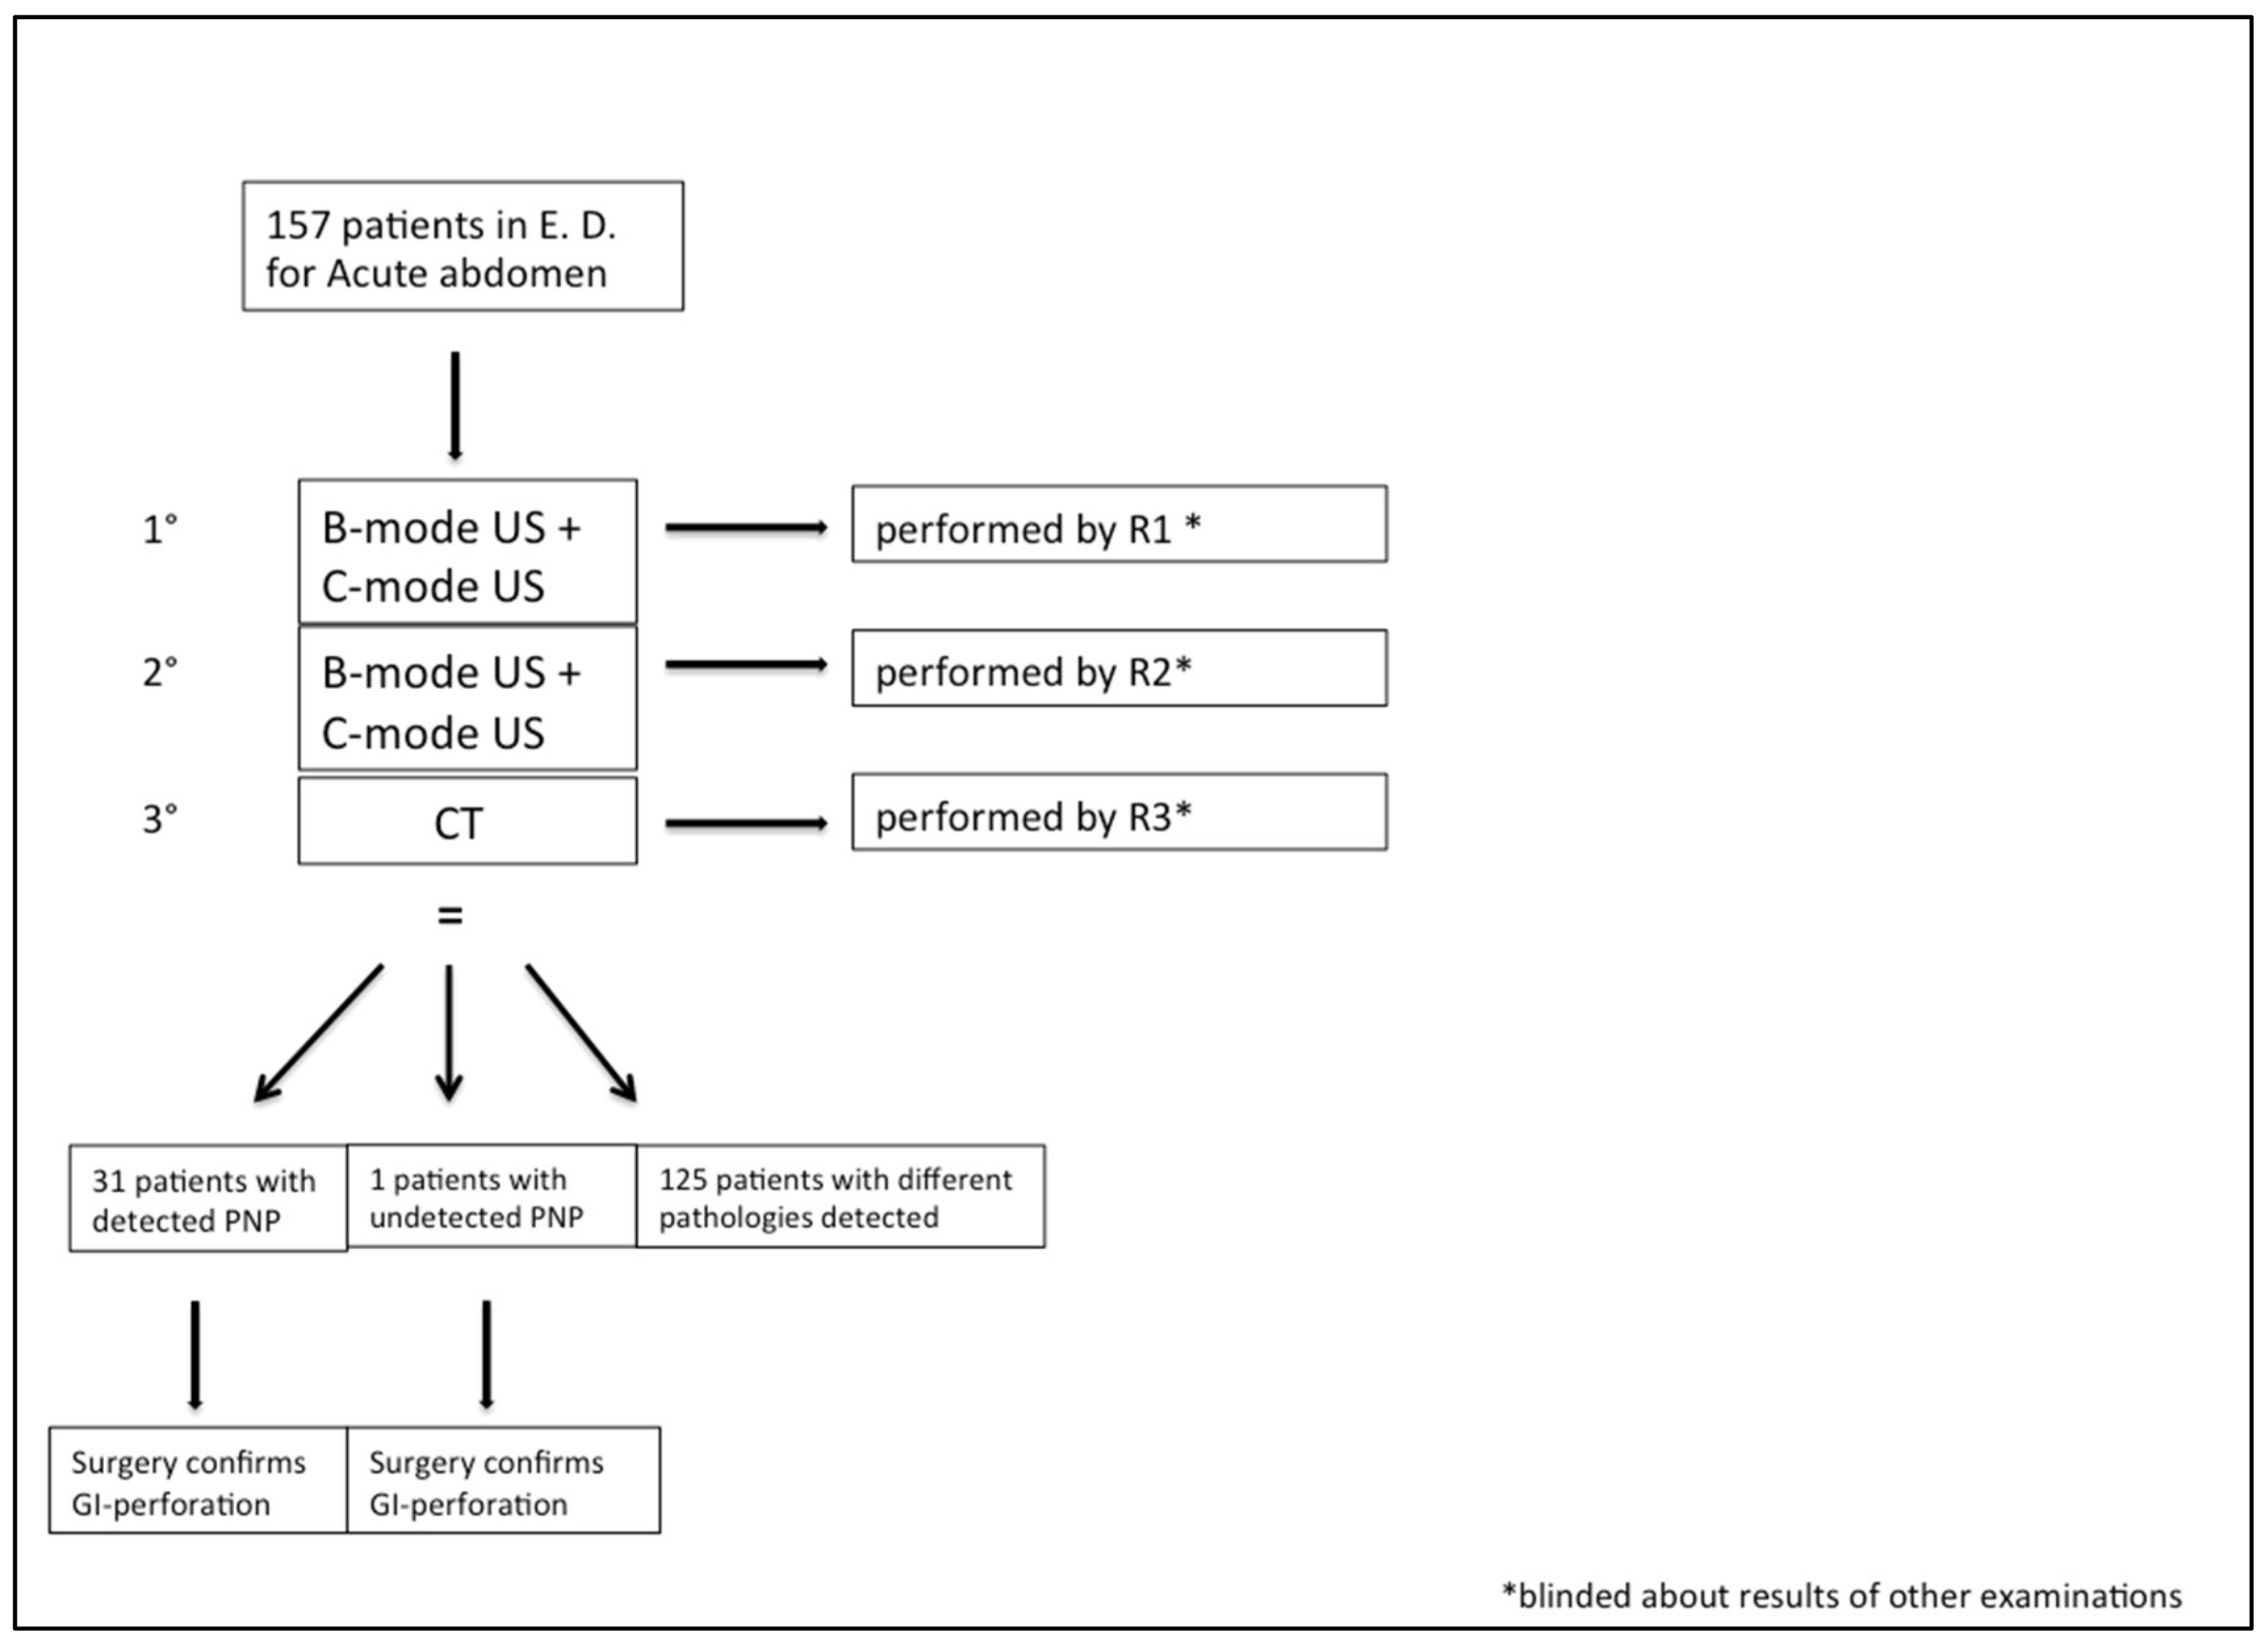

Our study included 157 consecutive patients who arrived in our emergency department with acute abdomen between April 2018 and October 2019. Hemodynamic instability and renal failure were considered exclusion criteria. All the included patients underwent US examination first, divided into two steps, and then a CT examination (

Figure 1). This workflow did not cause any significant time delay in the diagnosis and management decision process.

The US examination was performed by two different radiologists with no less than 5 years of experience in the emergency department (R1 and R2); CT evaluation was performed by a radiologist with 25 years of experience (R3).

The US examination was divided into two steps, consisting, first, of an examination performed using baseline US (B-mode), and a second examination using the mentioned US technology consisting of C-mode, with no contrast media administration, to focus on the free air detection. R1 and R2 conducted the two steps of the US examination for each patient; the interobserver concordance rate was calculated to explore the diagnostic performance and reproducibility.

All patients underwent CT examination after the US study was performed by R1 and R2 and the CT was examined by R3. Radiologists were blinded to the results of the other examinations. Since CT is considered as the gold standard in free air detection, the statistical analysis allowed us to estimate the sensitivity, specificity and diagnostic accuracy for CT, US B-mode and C-mode. Positive and negative predictive values of US B-mode and C-mode were also evaluated. Written informed consent was obtained from each patient.